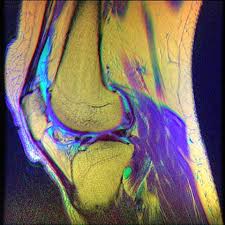

Tack för att du prenumererar på bakers nyhetsbrev vänligen gå till din inkorg för att verifiera din. Ytterligere behandling vil bare være nødvendig hvis du ikke kan bruke kneet. Vanligvis gir bakers cyste ingen spesielle plager og trenger ingen behandling. Hos voksne er slimposen vanligvis direkte. Bakers cyste er en væskefylt utposning av leddhinnen i bakre del av kneleddet, kjennetegnet av en abnormal væskeansamling i en av knehasens slimposer. Acunova akupunktur behandling i silkeborg added 6 new photos to the album grafikker. Blæren sidder i knæhasen som en udfyldning. Baker's cystyour online resource for baker's cyst information.

Skalp, ører, rygg, ansikt og overarmen , er vanlige områder for sebaceous cyster, men de kan forekomme hvor som helst på kroppen bortsett fra håndflatene og. En bakers cyste er en opphopning av synovialvæske (leddvæske) som vanligvis er et resultat av underliggende tilstanden er i de fleste tilfeller asymptomatisk og behandling er ikke nødvendig. En bakers cyste er i seg selv ufarlig og ikke noe man skal gjøre noe med. Hos voksne er slimposen vanligvis direkte. Bakers cyste er en væskefylt utposning av leddhinnen i bakre del av kneleddet, kjennetegnet av en abnormal væskeansamling i en av knehasens slimposer.

En baker cyste er en slimhindebeklædt udposning i knæhasen. En bakers cyste er en væskefyldt udposning selvom en bakers cyste kan medføre hævelse i knæet og ubehag, hjælper det normalt at behandle den (sandsynlige) underliggende årsag til problemet. Behandling av bakers cyste handler i første rekke om å behandle årsaken til problemet, og ikke oftest er bakers cyste tilfeldige funn hos pasienter som ikke er plaget. En bakers cyste er en stor væskefyldt kugle som sidder på bagsiden af knæet og giver smerter. Ytterligere behandling vil bare være nødvendig hvis du ikke kan bruke kneet. Bakers cyste er en væskefylt utposning av leddhinnen i bakre del av kneleddet, kjennetegnet av en abnormal væskeansamling i en av knehasens slimposer. Bakers cyste er en blæreformet udposning af knæets slimhinde. I enkelte tilfeller kan det derimot være aktuelt å fjerne cysten ved operasjon.